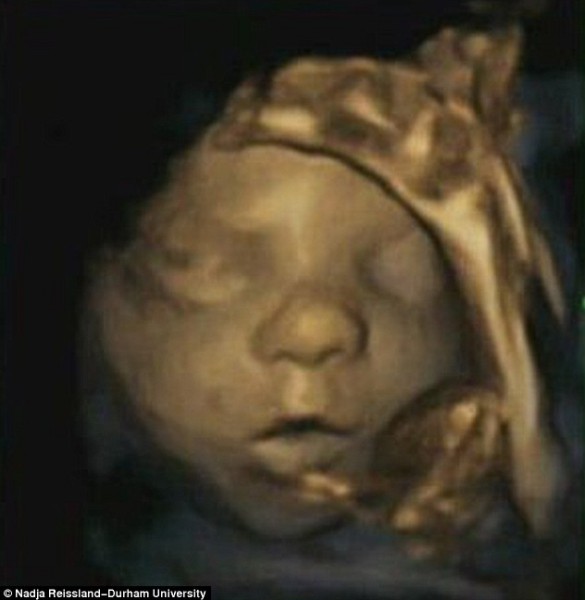

كشف فريق من العلماء والباحثين بجامعة درهام البريطانية عن مفاجأة كبيرة هى الأولى من نوعها على الإطلاق، حيث أشاروا أن الجنين يتمرن على الابتسامة داخل رحم أمه استعداداً للقاء أبويه، وذلك حسبما أظهرت مجموعة من الصور رباعية الأبعاد “4D”، والتى سلطت الضوء على تعبيرات وجوه مجموعة الأجنة قبل حدوث الولادة بفترات تصل إلى 16 أسبوعا.

وعلق علماء النفس بجامعة درهام البريطانية على تلك الصور غير المسبوقة، مشيرين أن الأجنة تتدرب وتمارس كيفية التعبير عن مشاعرها، وخاصة أنهم على موعد قريب للقاء الأب والأم عقب الولادة مباشرة، وأثبتوا أن قدرات الطفل العقلية على إظهار عواطفه ومشاعره تتطور فى وقت مبكر جداً من حياته، وهو ما يعد أمراً مثيراً للغاية.

يذكر أنه تم التقاط هذه الصور رباعية الأبعاد باستخدام أشعة الموجات فوق الصوتية لحوالى 15 جنينا، تتراوح أعمارهم ما بين 24 إلى 36 أسبوعاً من بداية الحمل.